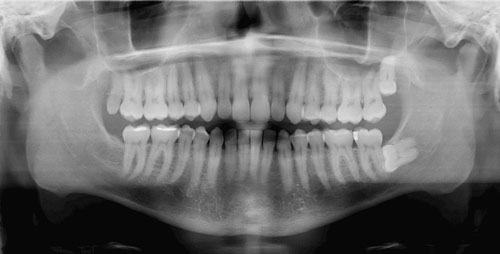

Oral Diagnoz ve Radyoloji